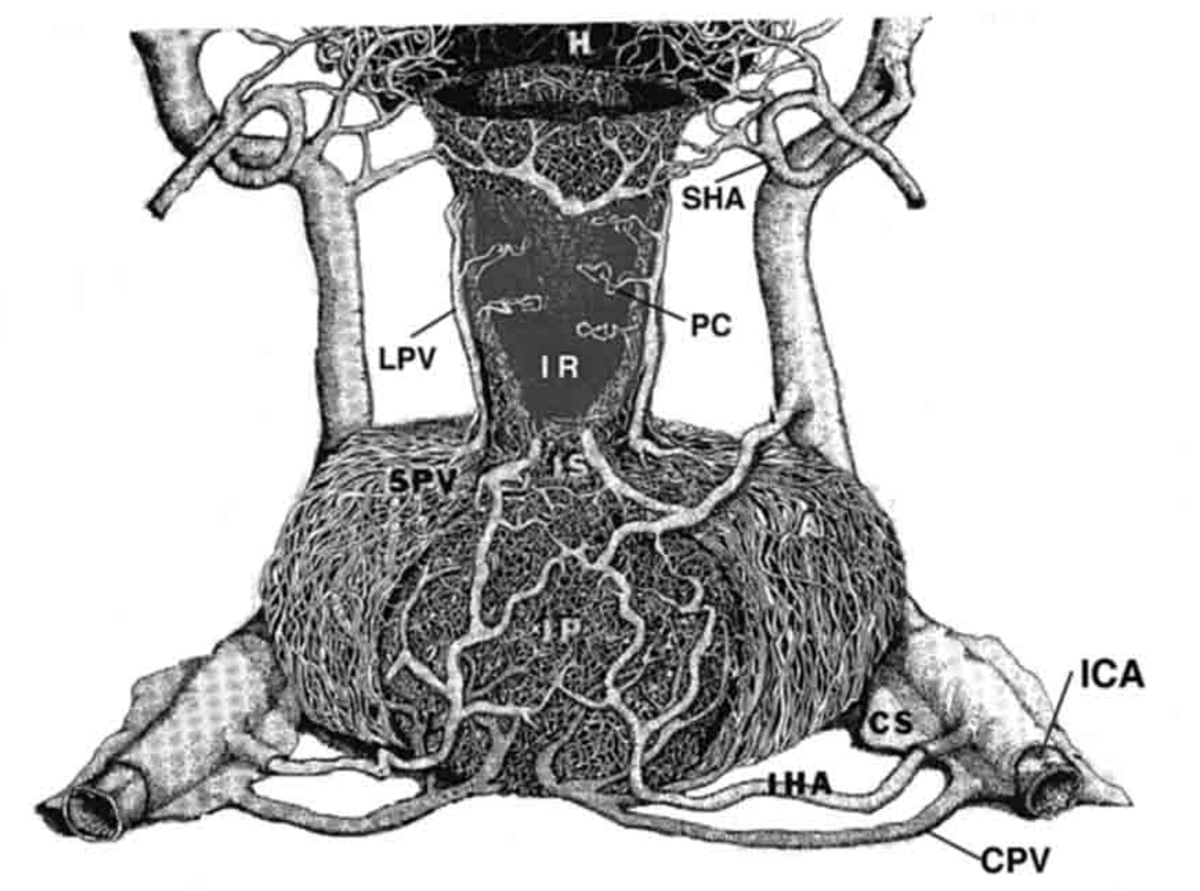

Fig. 9. Drawing of the vasculature of the primate anterior and posterior pituitary gland. A portion of the pituitary stalk (I) has been cut away to visualize the infundibular recess (IR) and portal capillaries (PC). CPV = confluent pituitary veins, CS = cavernous sinus, H = hypothalamus, IC = internal carotid artery, IHA = inferior hypophysial artery, IP = infundibular processes or posterior pituitary, LPV = long portal veins, SHA = superior hypophysial artery, SPV = short portal veins. (From Lechan RM, Functional Microanatomy of the Hypophysial-Pituitary Axis, in Melmed, S (Ed), Oncogenesis and Molecular Biology of Pituitary Tumors, Frontiers of Hormone Research, 20: 2-40, 1996.)